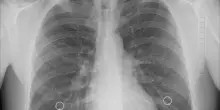

Influenza, Bassetti: "In ospedale 20enne con pericardite-miocardite, giovani vaccinatevi"

(Adnkronos) - "E' tutt'altro che un'infezione banale, può colpire tutti gli organi e causare complicanze gravi"